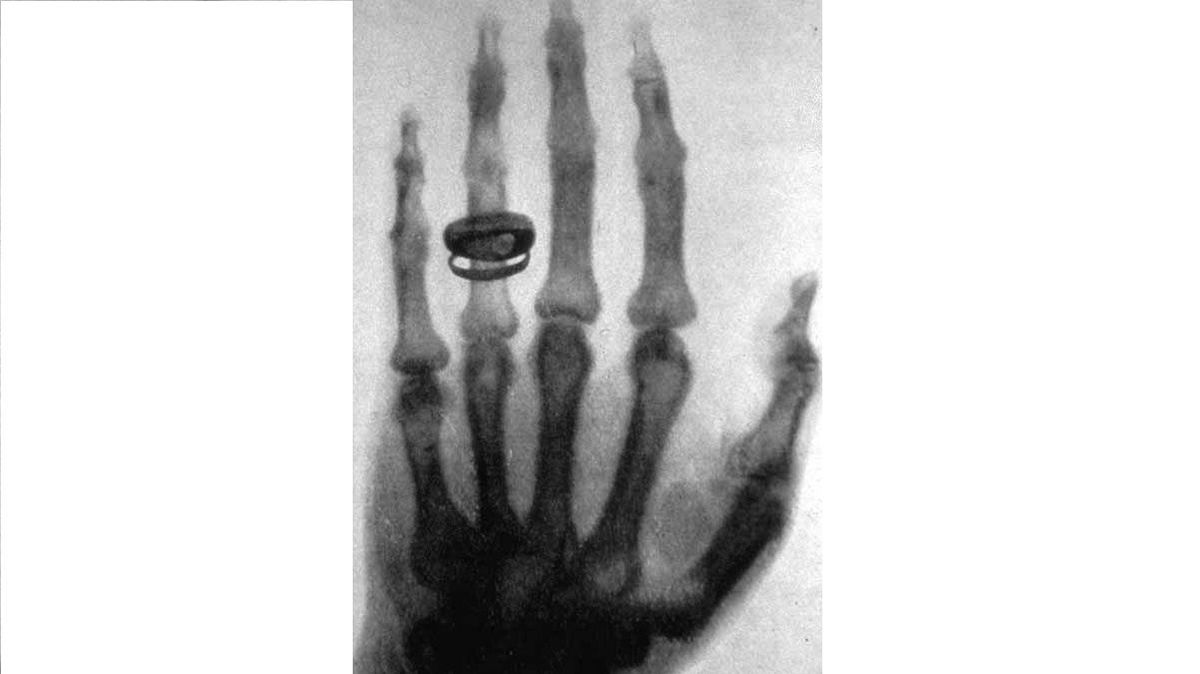

Dnes před 130 lety zahajuje W. C. Röntgen pokusy se zářením z Lenardovy a Crooksovy trubice. Objeví tak zobrazovací metodu, která po něm bude pojmenována a taky za ni dostane úplně první Nobelovu cenu za fyziku.